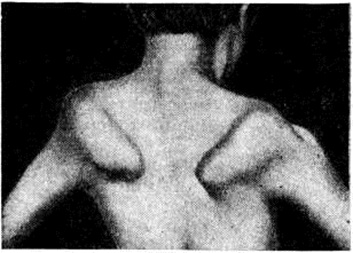

Поражение поперечнополосатых мышц глаз приводит к частичной или полной офтальмоплегии, птозу, экзофтальму, лагофтальму. Поражение мышц мягкого неба, глотки и гортани проявляется нарушением глотания и фонации. Симптомы поражения мышц плечевого пояса — ограничение объёма активных движений в проксимальных отделах рук, отставание лопаток от туловища — симптом «крыловидных лопаток» (рисунок 4), отсутствие сопротивления мышц плечевого пояса при поднимании больного за подмышки — симптом «свободных надплечий» (рисунок 5.); плечи больного поднимаются вверх, а голова как бы проваливается между ними. Атрофия длинных мышц спины и тазового пояса проявляется нарушением осанки и походки: выражен гипер лордоз позвоночника, голова несколько запрокинута назад, туловище при ходьбе ритмично раскачивается — «утиная походка». Затруднено поднимание по лестнице, вставание из сидячего положения. Для того чтобы принять вертикальное положение, больной вынужден прибегать к помощи рук, опираясь на соседние предметы или собственные бедра,— вставание «лесенкой» (симптом «лестницы» — рисунок 6, я, б, в). При атрофии косых мышц живота наблюдается симптом «осиной талии». Нарушение походки по типу «степпажа» или «петушиной походки» характерно для локализации миодистрофического процесса в мышцах голени и стопы. Поражение мышц приводит к ограничению подвижности суставов вплоть до образования контрактур. Присоединяющаяся, как правило, в поздней стадии заболевания легочно-сердечная недостаточность является следствием миодистрофического процесса в миокарде и дыхательной мускулатуре. При электромиографическом исследовании выявляют снижение амплитуды осцилляций, высокую частоту полифазных потенциалов, укорочение времени отдельных осцилляций.